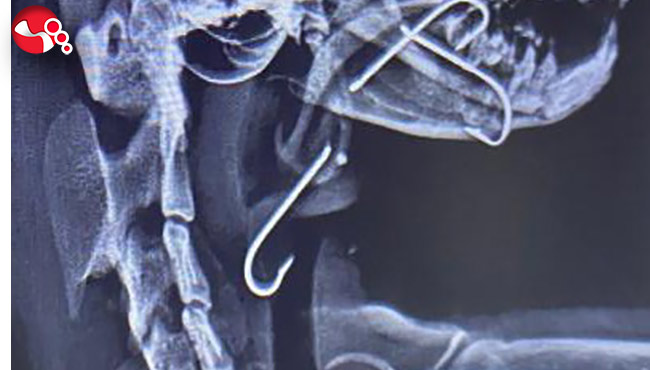

Kilimli ilçesinde bir sokak kedisinin ağzında kanca olduğunu gören vatandaşlar durumu hayvansever Seda Mercan'a iletti. Kediyi bulan Mercan, zabıta ekiplerinden yardım istedi. Veteriner hekime getirilen sokak kedisinin röntgeninde boğazına saplanmış üç tane olta kancası olduğu tespit edildi. Ameliyata alınan kedinin boğazındaki kancalar çıkartıldı. Yaklaşık bir saat süren ameliyatta kancaların derine saplandığı görüldü. Ameliyattan sonra kedi sağlığına kavuşurken veteriner hekim Furkan Alkan, süreci şöyle aktardı:

"Vaka geldiği zaman ağzında salya akıntısı ile geldi. Üç günden beri bu haldeymiş. İlk yaptığımız muayenede kancanın bir kısmını gördük ve hemen röntgeni çektik. Röntgende 3 tane kancanın boğazına takıldığını gördük. Endoskopi yardımıyla 3’ünü birden çıkardık. Üçü de çok derine saplanmıştı. Yarım saat bir saatlik bir operasyonla arkadaş sağlığına kavuştu. Ya balık alırken ya da balıkçılar tarafından atılan balığı kaparken kancayla beraber kaptı. Kancaları yuttu. Oraya saplandığı için de ne ağızda kaldı ne de mideye gitti. 3-4 günden beri enfeksiyonlu ağız akıntısı varmış, kliniğimize gelip tedavisini gördü. 4-5 yaşlarında sokak hayvanı. Bir hayvansever tarafından getirildi. Masraflarını hayvansever karşılıyor."